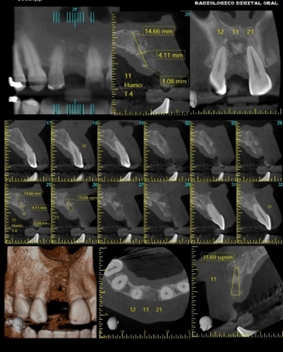

Estudio para implantes

La planificación para un implante dental comienza con una evaluación inicial del paciente, donde se recopilan datos sobre su historial médico y oral…